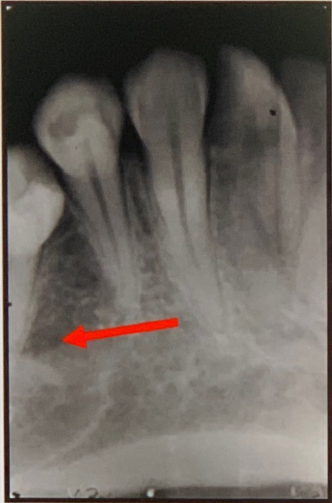

95. What is showing by red arrow?

External Oblique Ridge a continuation of the anterior border of the mandibular ramus. It follows an anteroinferior course lateral to the alveolar process.